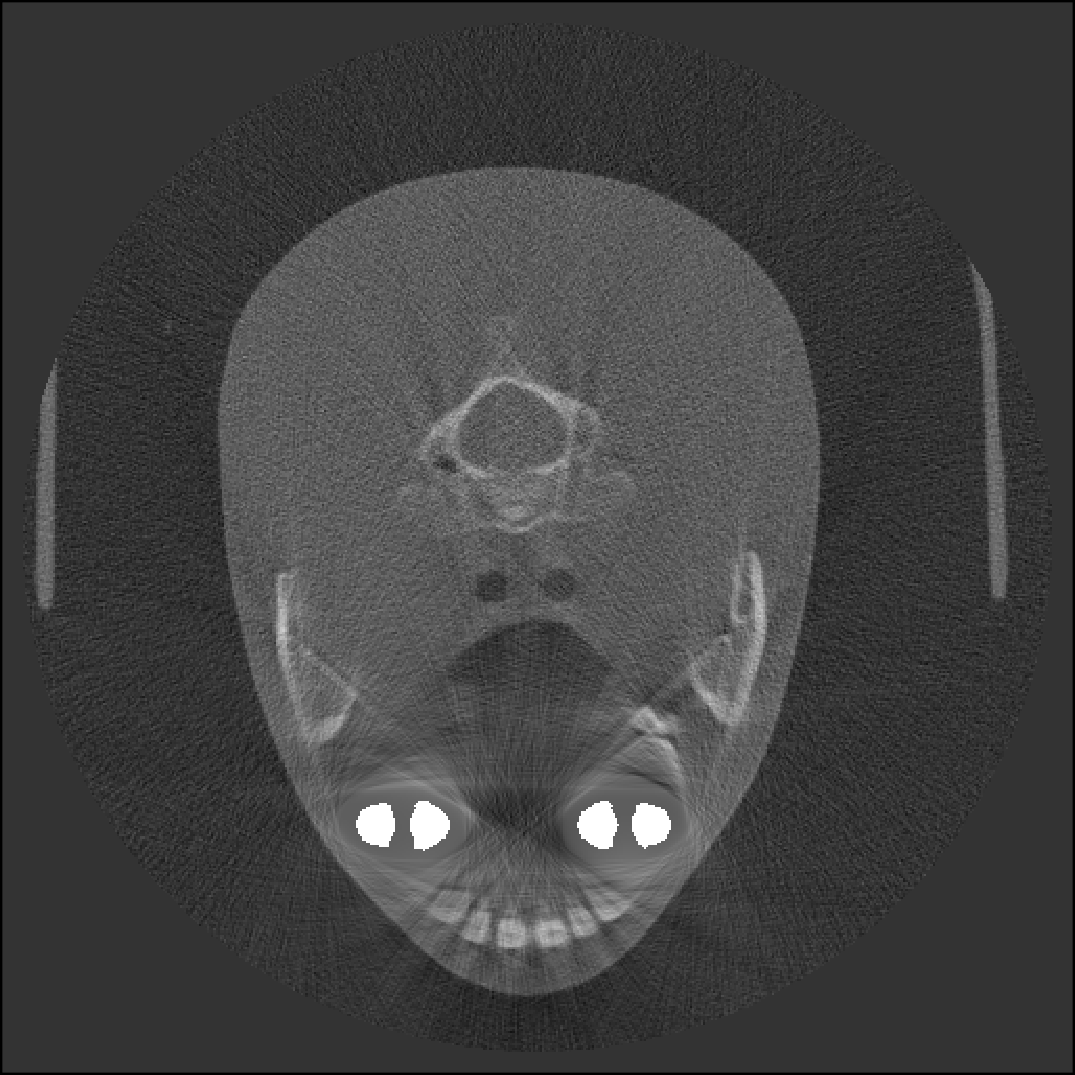

We computed the uncorrected FDK reconstruction, the image-domain hard-thresholding–based MAR reconstruction, and the proposed projection-domain complex wavelet MAR reconstruction for datasets (I–V). Fig. 4 shows selected slices from the reconstruction volumes for each dataset, displayed using identical windowing. The quantitative results of the metal segmentation are reported in Table 1 for datasets (I) and (II).

First of the experimental metal datasets, dataset (III) provides a simple test case for severe artifacts caused by an amalgam filling. As in dataset (I), the HT-MAR approach reduces artifacts in the uncorrected FDK reconstruction. However, residual artifacts persist due to missed metal voxels near the metal boundaries in the segmentation. The CW-MAR method removes nearly all artifacts, particularly in the sagittal and coronal slices.

Dataset (IV) produces substantial artifacts in the FDK reconstruction. For HT-MAR, identifying a suitable threshold level is challenging, as the HU values of the artifacts overlap with those of the actual metal features. This leads to poor metal segmentation. In contrast, CW-MAR removes most artifacts and recovers the general shape of the prosthesis.